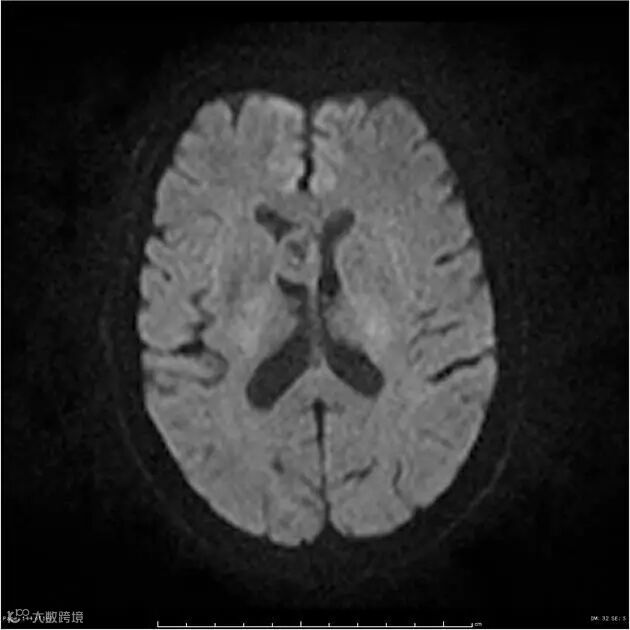

ADC